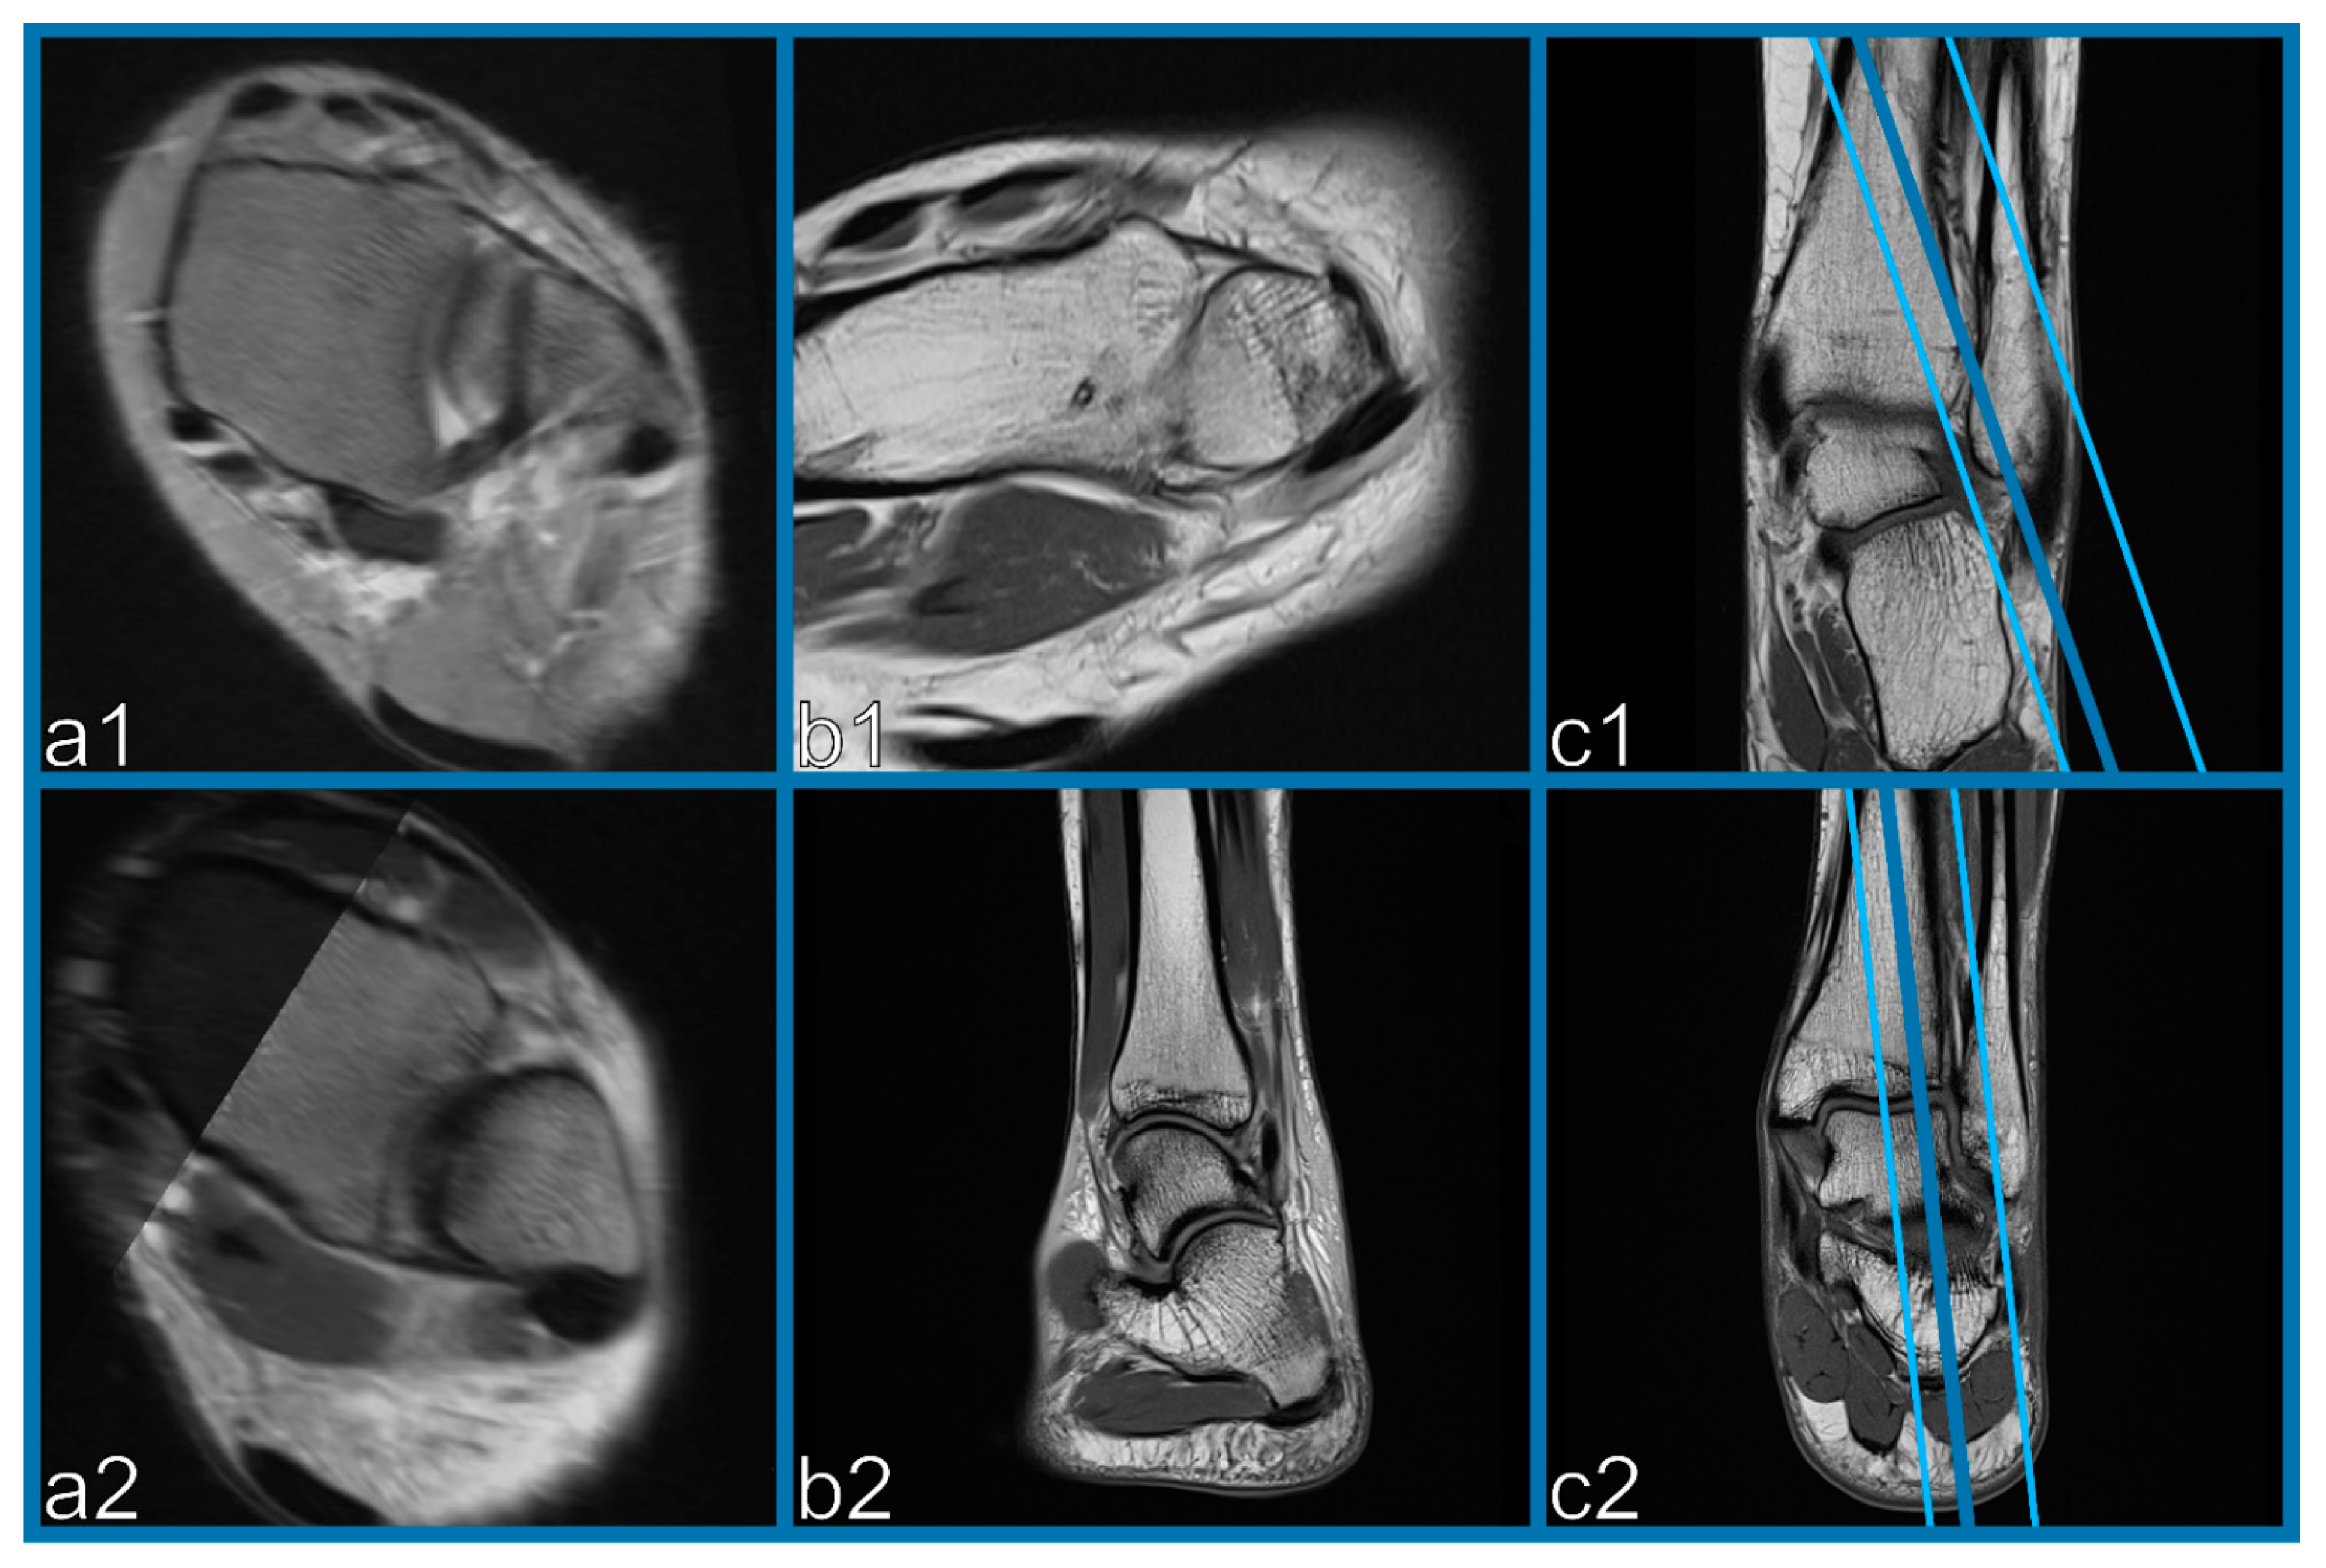

2.4. Reconstruction of Oblique-Fusion Reconstruction Images

2.5. Experimental Setup